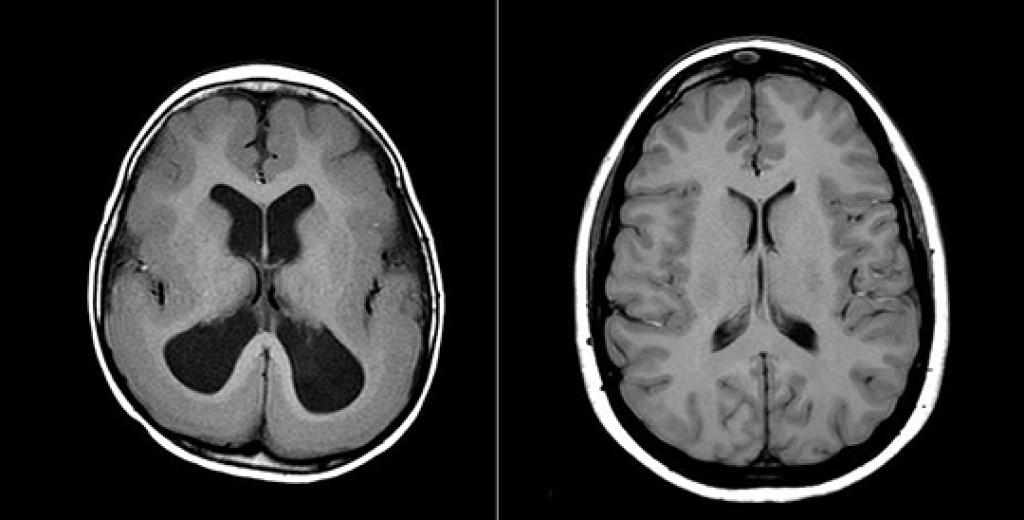

with lissencephaly are living longer due to therapies and better management of their condition so families have to make plans for the long-term care of their children. These photos illustrate the differences between a brain affected by lissencephaly (left) and a normal brain (right). For more information about Texas Children's Neurology Department, visit here. And to watch ABC 13 KTRK's news report, visit here.